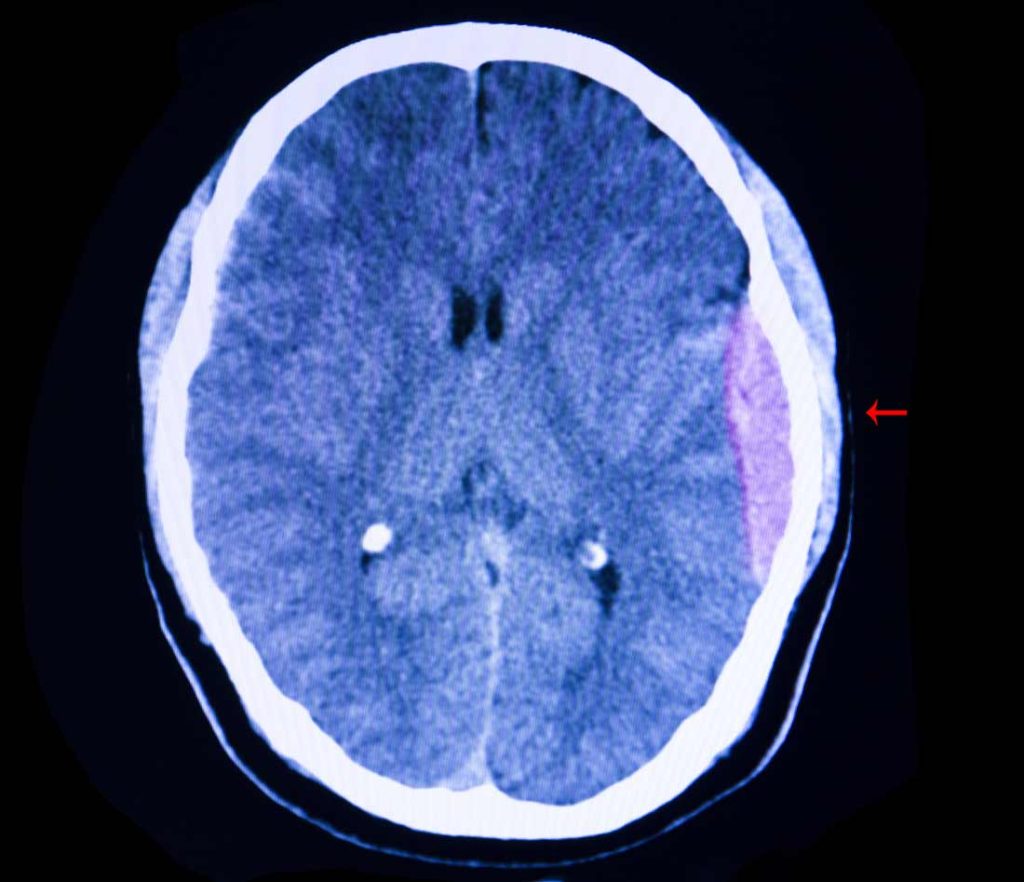

Hematoma subdural: definição, causas, sintomas, tratamento, diagnóstico, evolução e possíveis complicações - O hematoma é uma coleção sanguínea resultante de uma hemorragia (extravasamento de sangue) nos espaços meníngeos, entre a aracnoide e a dura-máter (abaixo da dura-máter; subdural). Para melhor entender o que ocorre, deve-se lembrar de que há um espaço virtual entre as.. 4. Idade avançada: O envelhecimento dos vasos sanguíneos pode torná-los mais frágeis e propensos a rompimentos, aumentando o risco de hematomas subdurais em pessoas idosas. Sintomas do Hematoma Subdural. Os sintomas de um hematoma subdural podem variar dependendo da gravidade e da localização do sangramento.

Declara, outrossim, que o(a) referido(a) médico(a), atendendo ao disposto nos artigos 31 e 34 do Código de Ética Médica e no artigo 9o da Lei 8.078/90 e após a apresentação de métodos alternativos, sugeriu o tratamento médico cirúrgico de TRATAMENTO CIRURGICO DO HEMATOMA SUBDURAL CRÔNICO, antes apontado, apresentando informações.. O hematoma subdural tem evolução variável, a depender do tamanho do hematoma, da idade do paciente, dos sinais/sintomas neurológicos à apresentação, da presença de coagulopatia ou neoplasia subjacentes e de lesões associadas. Deve-se considerar a terapia profilática de uma semana com antiepilépti.